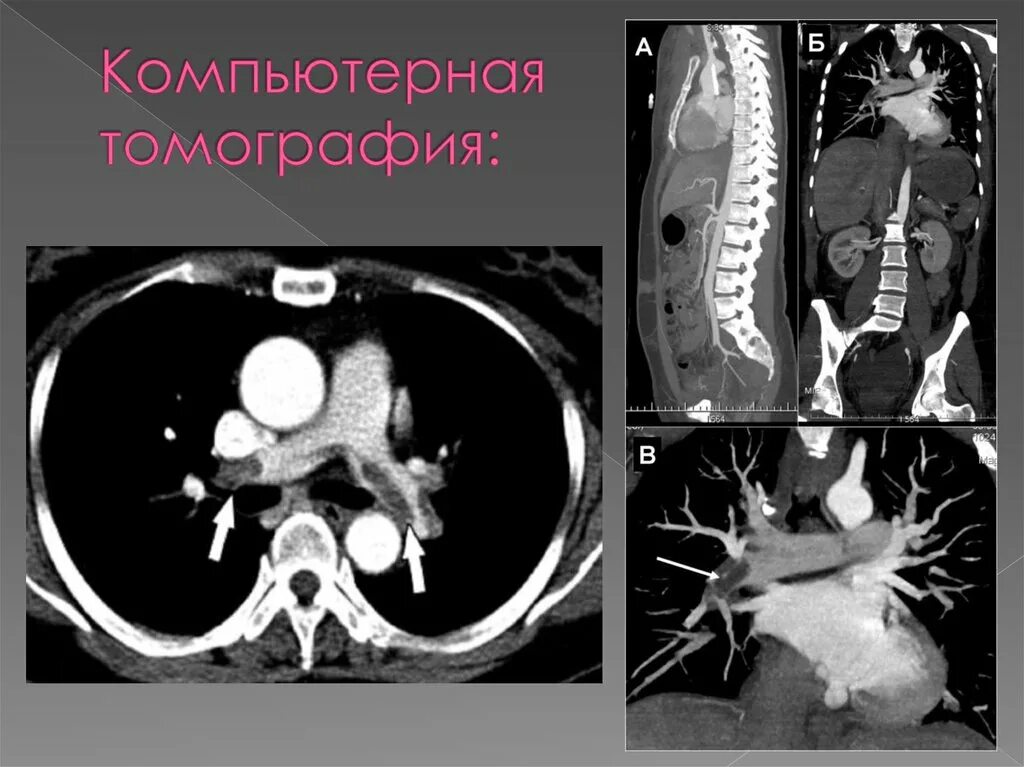

Легочный ствол на кт